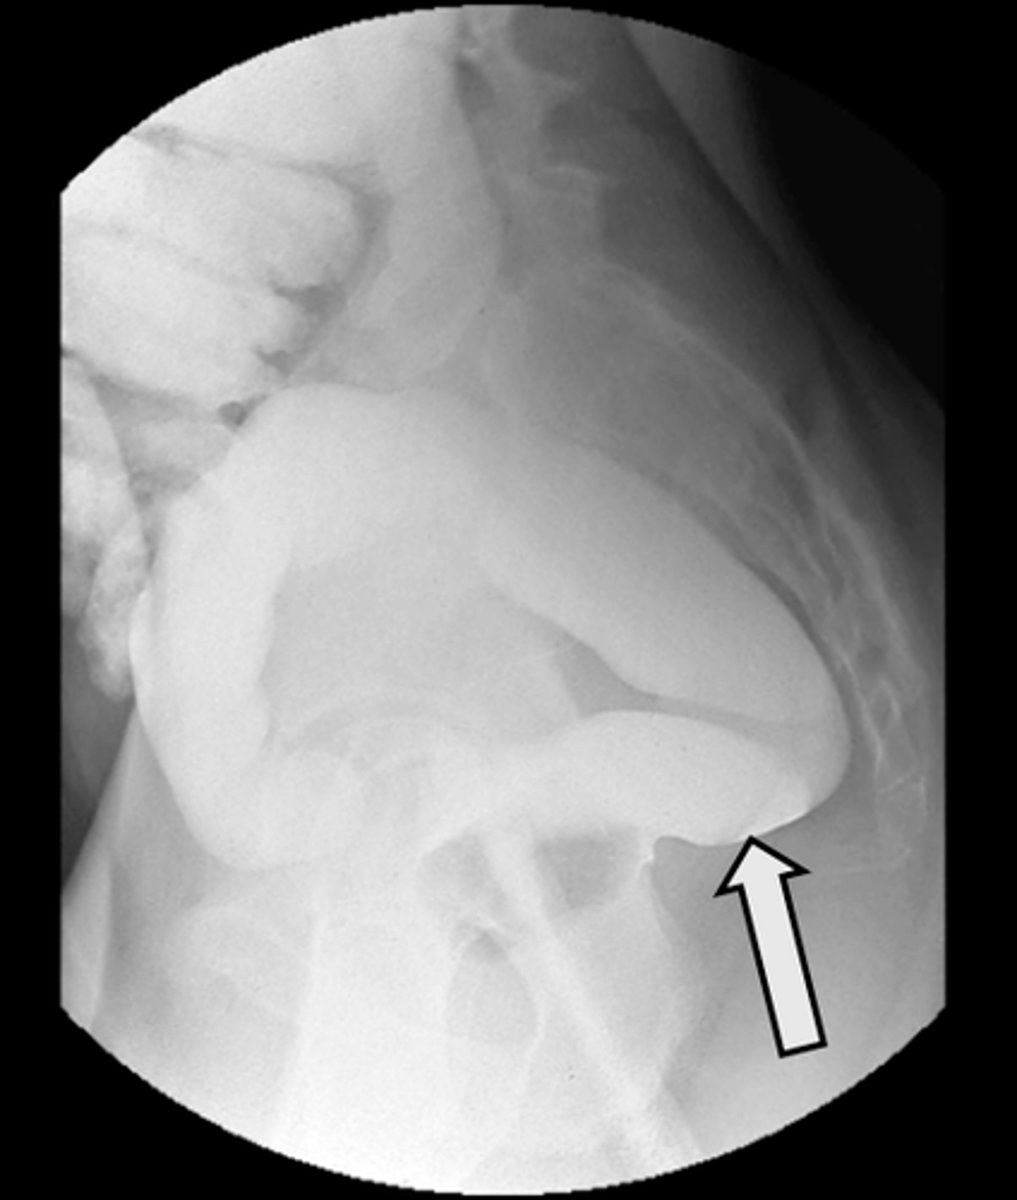

Lateral rectum with barium enema

What is the image?

<p>What is the image?</p>

Rectal tube

What is indicated in the image?

<p>What is indicated in the image?</p>

Rectum